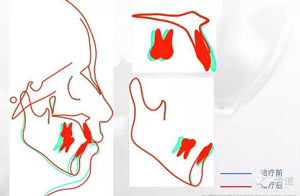

治療前后重疊圖

矢狀向、垂直向及開(kāi)合:上頜磨牙壓低及下頜磨牙前移產(chǎn)生的楔形效應(yīng),上前牙適量?jī)?nèi)收產(chǎn)生的鐘擺效應(yīng),以及肌功能訓(xùn)練的綜合作用解除了患者的開(kāi)合,并使下頜逆時(shí)針旋轉(zhuǎn),矯治后患者的側(cè)貌得到極大改善,達(dá)到了近乎“頦成形”的效果。